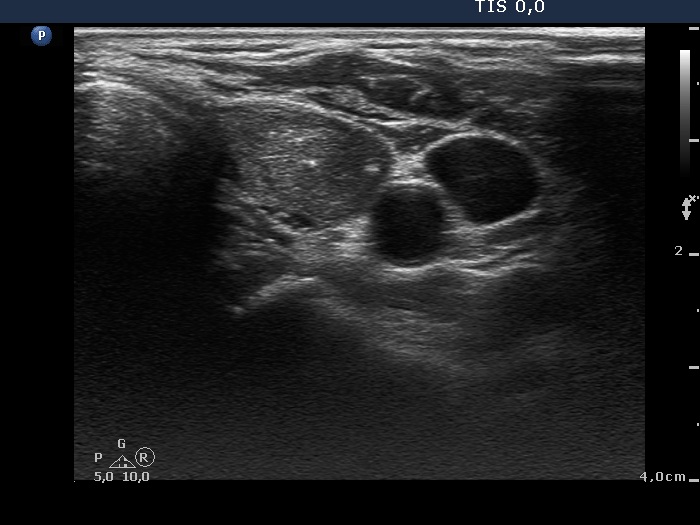

Right lobe, longitudinal scan